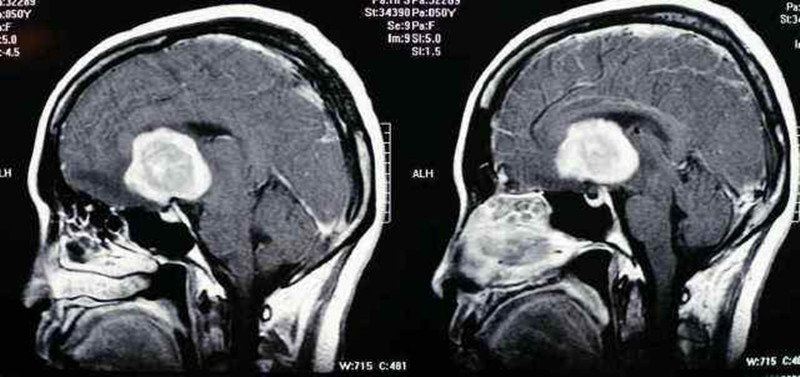

中枢淋巴瘤核磁图片